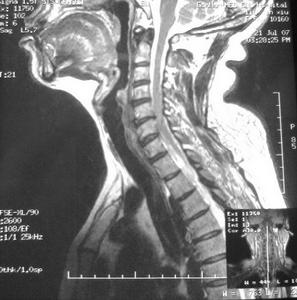

頸椎平掃

頸椎平掃相關詞條